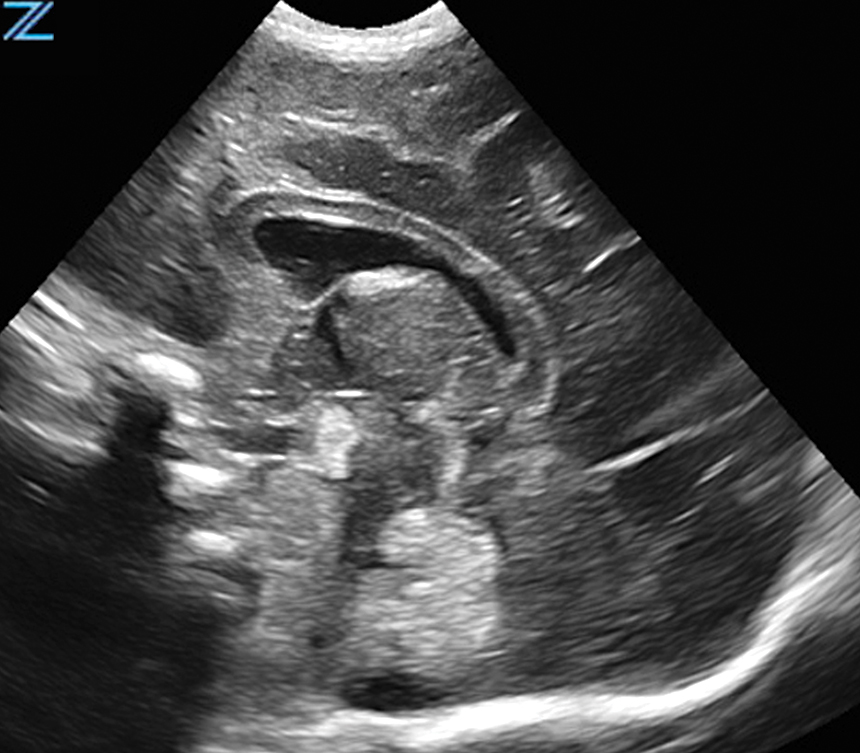

Normal Neonatal Brain Perfusion | C10-3